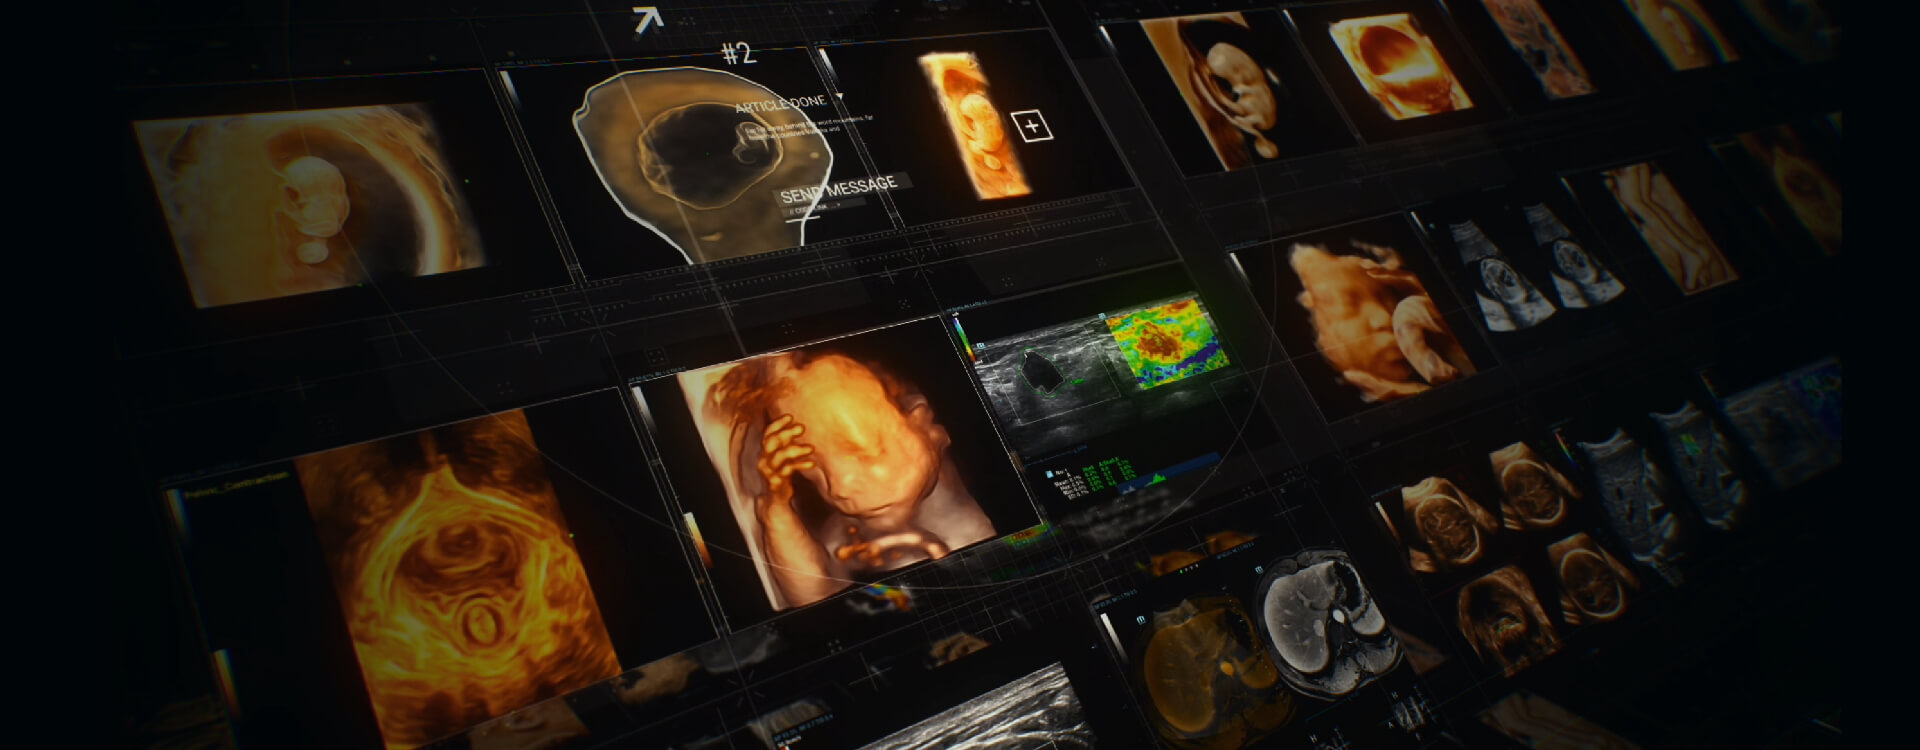

OptimizaciĂłn del rendimiento clĂnico y los resultados de los pacientes

Ayudando a los hospitales a crear beneficios de gran escala